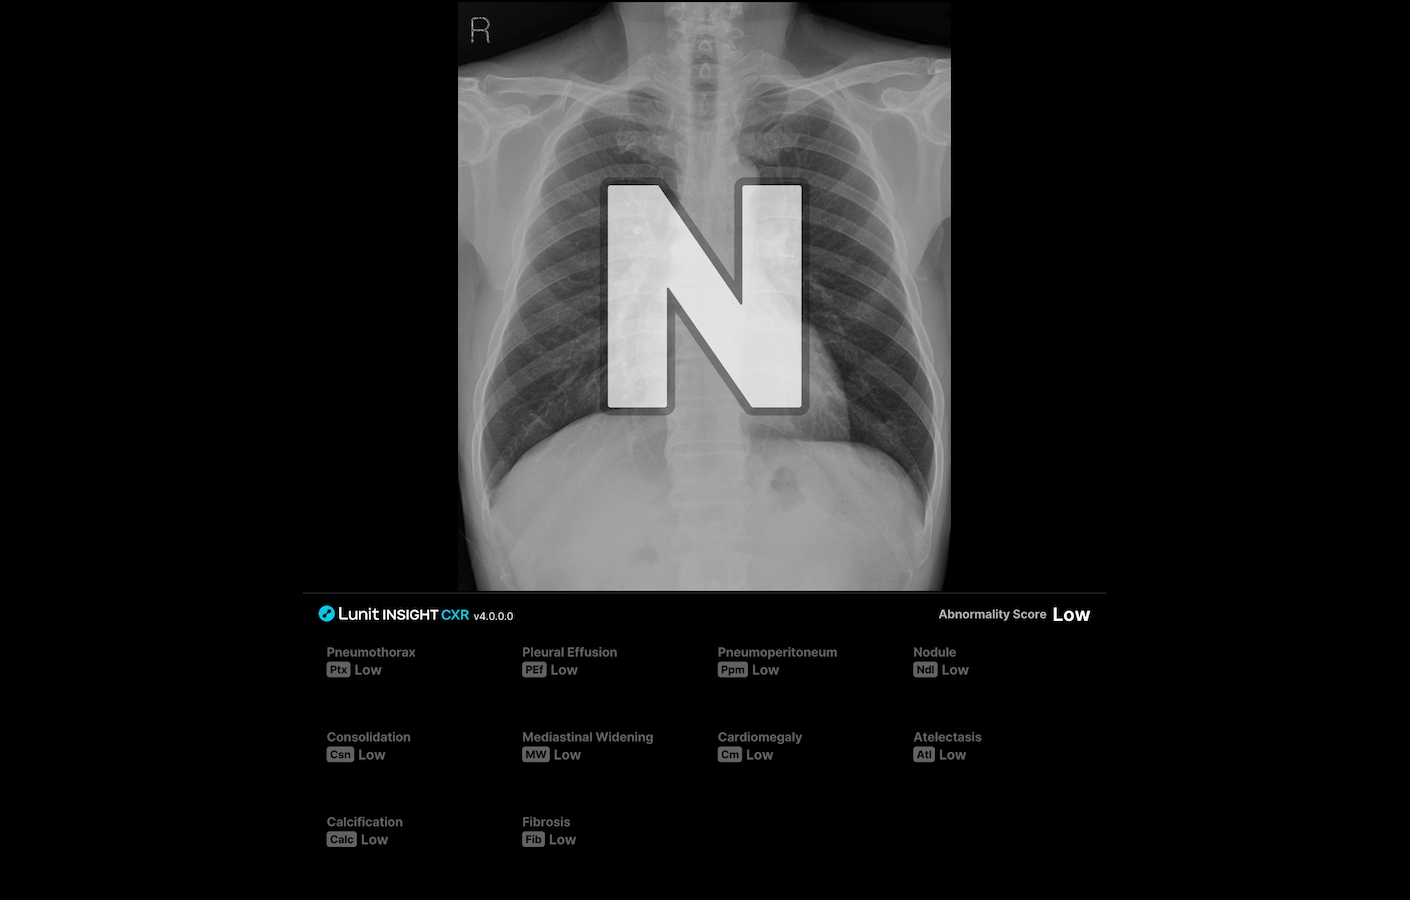

특히 루닛의 Dual AI Engine(Abnormality AI Engine, Normal Flagging AI Engine)을 기반으로, 정상 소견을 분류하고 의심 소견이 있는 영상을 표시해 판독 업무 효율 향상¹에 도움을 줄 수 있습니다.

루닛 인사이트 CXR4는 결절, 경화, 기흉, 흉막삼출, 무기폐, 기복증, 심장비대, 종격동 확장, 석회화, 폐섬유화 등 흉부 엑스레이에서 가장 흔하게 발견되는 10가지 비정상 소견을 진단·검출 보조하며, 폐결핵 선별을 지원합니다.